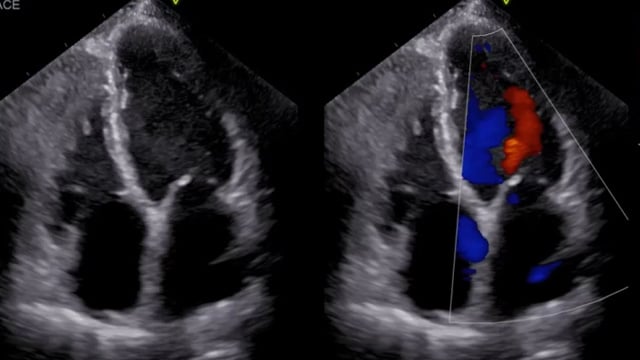

Transcatheter mitral valve-in-valve in prior degenerated mitral valve - LIVE Case

This educational session offers comprehensive guidance on transcatheter mitral valve-in-valve procedures for degenerated bioprosthetic mitral valves. Key learning points include valve sizing considerations, transeptal access techniques, and procedural steps distinct from standard transcatheter aortic valve implantation (TAVI), supported by detailed imaging analysis and a live case...